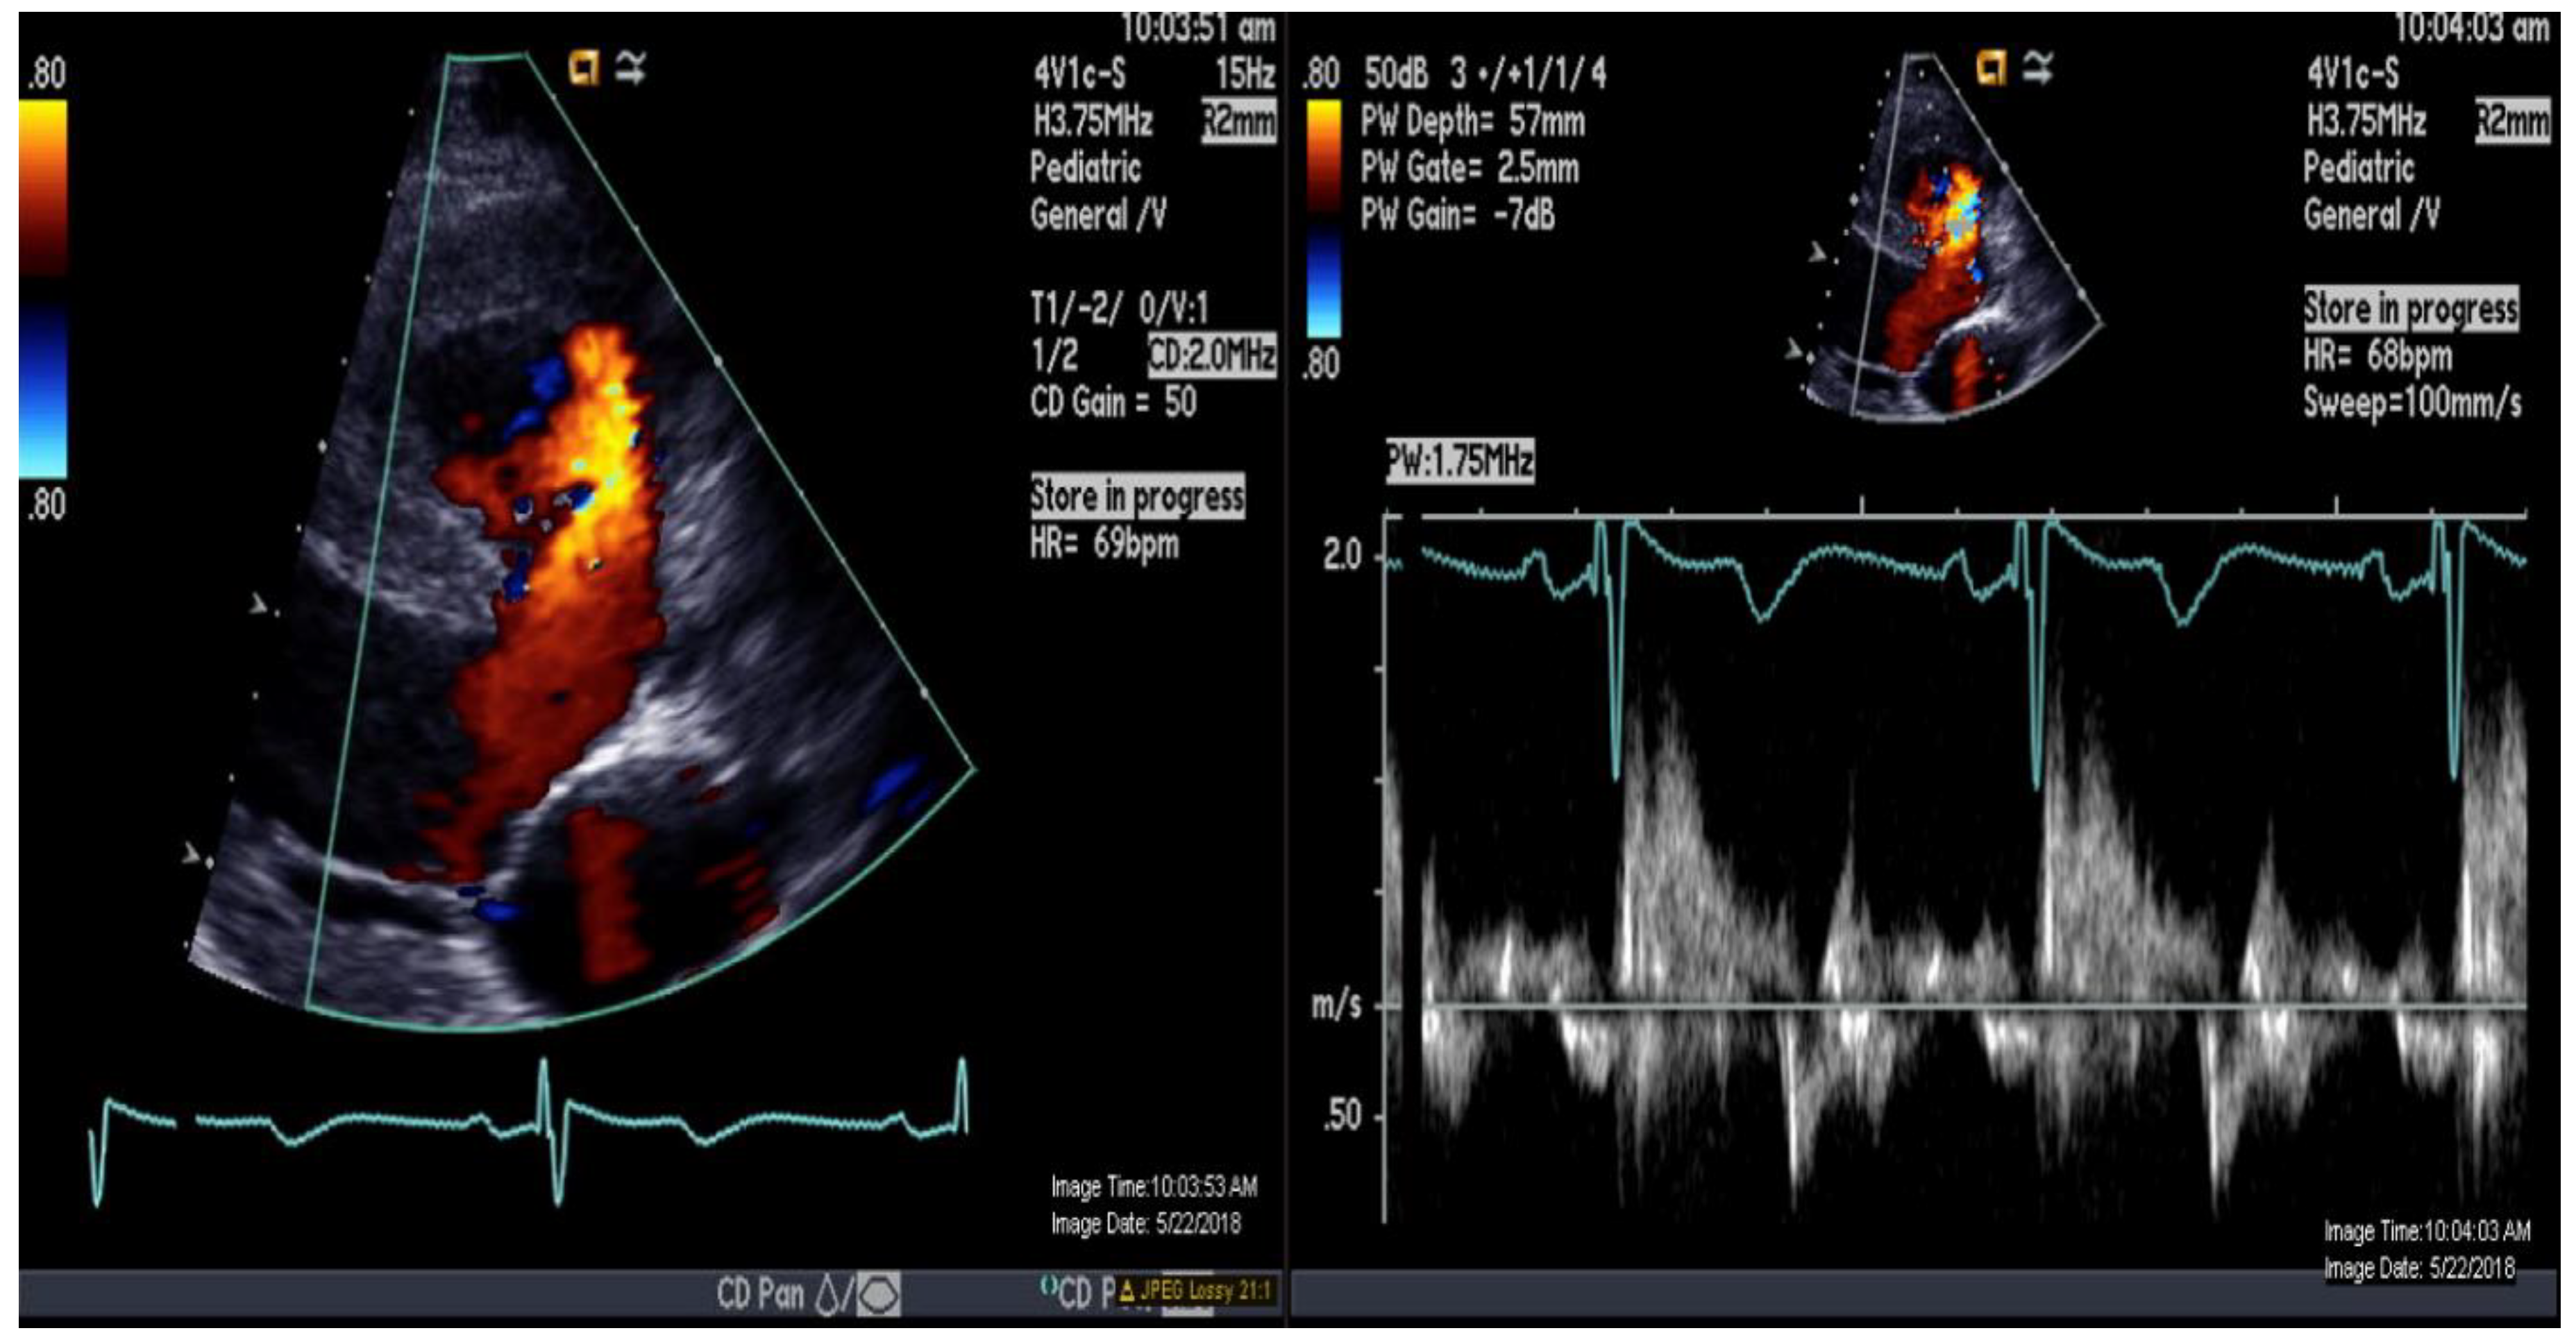

Figure 2.

Color-and-pulse Doppler showing bidirectional shunting across a large perimembranous ventricular septal defect.